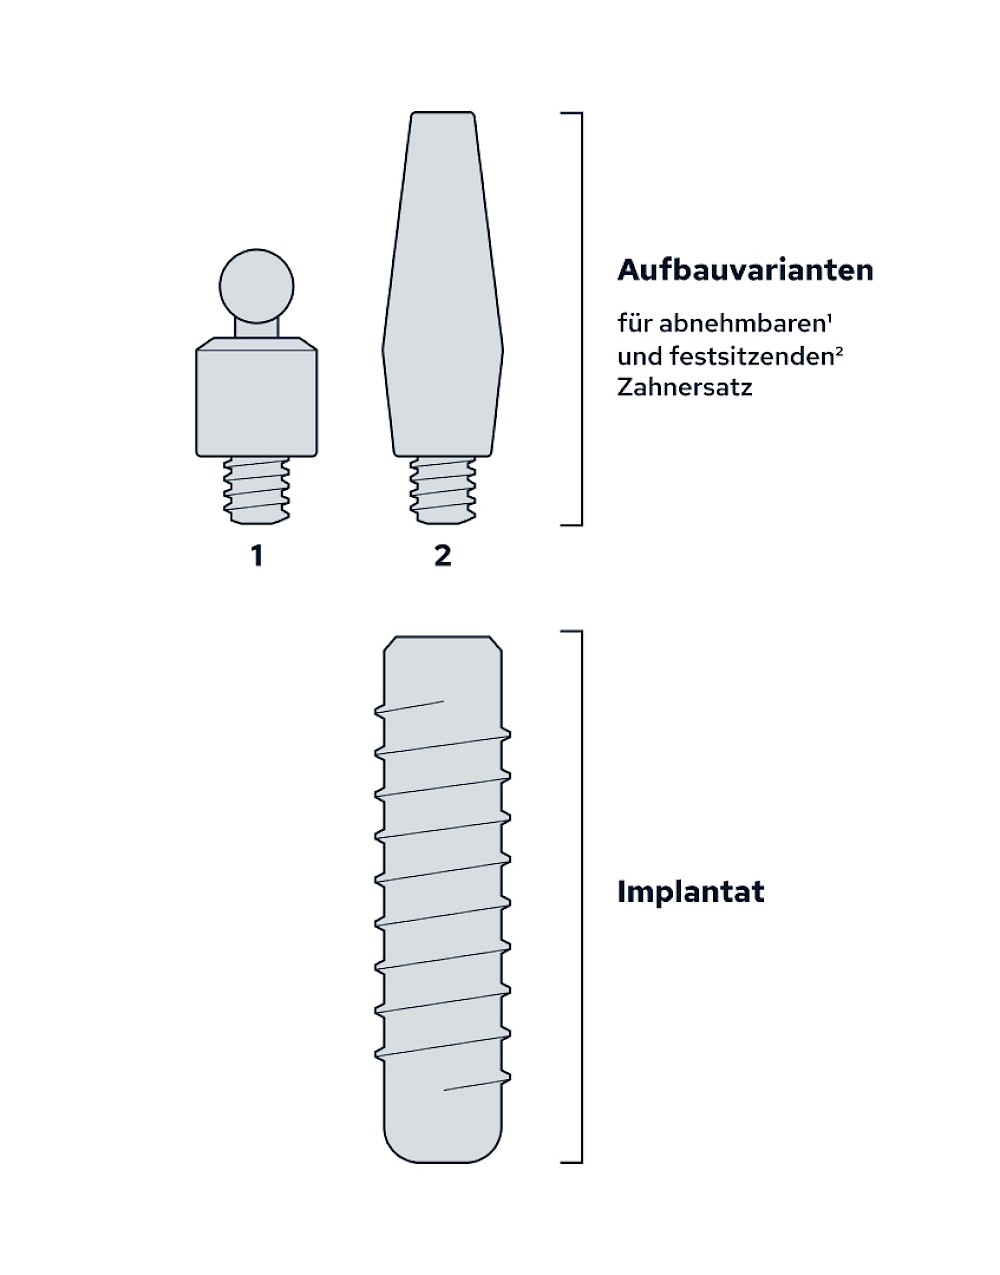

Implantat & Aufbau

Implantate sind künstliche Zahnwurzeln – meist aus Titanlegierungen, selten auch aus keramischen Werkstoffen. Gehen Zähne verloren werden diese Implantate in den Kiefer eingebracht. Nach einer gewissen Einheilzeit (3-6 Monate) im Knochen wird zunächst für ein bis zwei Wochen das Zahnfleisch im Bereich die Durchtritts-Stelle "geformt" und in der Folge der sogenannte Aufbau (Abutment) aufgeschraubt. Der Aufbau erlaubt dann die Befestigung einer Krone, Brücke oder Zahnprothese.

In seltenen Fällen sind Implantate samt Aufbau aus einem Stück gefertigt. Auch gibt es Situationen, die ein Früh- oder sogar eine Sofortbelastung erlauben - dann kann die Einheilzeit der Implantate in den Knochen verkürzt oder sogar gänzlich darauf verzichtet werden.

Implantat Aufbau